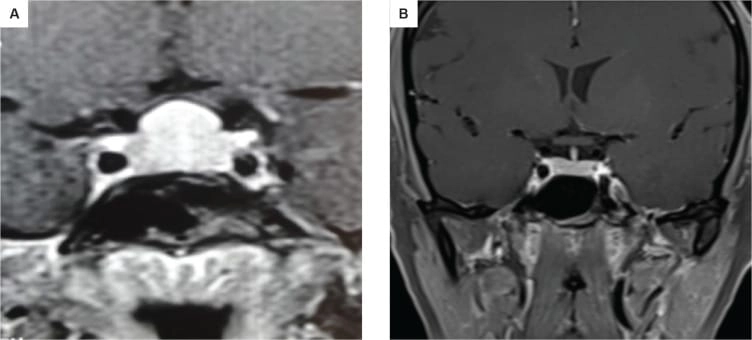

কেস ১: একজন ১৬ বছর বয়সী কিশোরী প্রাথমিক অ্যামেনোরিয়া ও খর্বাকৃতিজনিত কারণে এমআরআই করার পর একটি পিটুইটারি টিউমার শনাক্ত হয় এবং তাকে অস্ত্রোপচারের জন্য রেফার করা হয়। তবে তার রক্ত পরীক্ষায় পাওয়া যায় TSH ছিল 119.20 এবং Free T4 ছিল 4.14 pmol। এই অস্বাভাবিক মাত্রার কারণে এটিকে একটি থাইরোট্রোফ হাইপারপ্লাসিয়া হিসেবে বিবেচনা করা হয় এবং তার চিকিৎসা শুরু হয় এবং ৬ মাসের মধ্যে উচ্চতা ১২৪ থাকে বেড়ে ১৩১ সেমি হয় এবং তার ঋতু ও শুরু হয় এবং MRI-তে টিউমার সম্পূর্ণভাবে অদৃশ্য হয়ে যায়।

কেস ২: একই রকমভাবে, ১৫ বছর বয়সী আরও একজন কিশোরী অল্প উচ্চতা ও টিউমার সন্দেহে নিউরোসার্জেনের কাছে রেফার করা হয়। তার TSH ছিল 100 এবং MRI-তে একটি ডোম-আকৃতির টিউমার দেখা যায়। যাকে ওষুধের চিকিৎসায় সত্য জীবনে ফিরিয়ে আনা হয় এবং ৬ মাসে তার উচ্চতা বৃদ্ধি পায় ও নিয়মিত মাসিক শুরু হয়। MRI-তে টিউমার সম্পূর্ণ অদৃশ্য হয়ে যায়।

MRI-তে এই হাইপারপ্লাসিয়া সাধারণত গম্বুজ-আকৃতির ও সমমিত হয় এবং হোমোজেনাস সিগনাল ইন্টেনসিটি দেখায়, যেখানে সাধারণ নন-ফাংশনাল পিটুইটারি অ্যাডেনোমা নানা আকার ও অসমতা নিয়ে দেখা যায়।